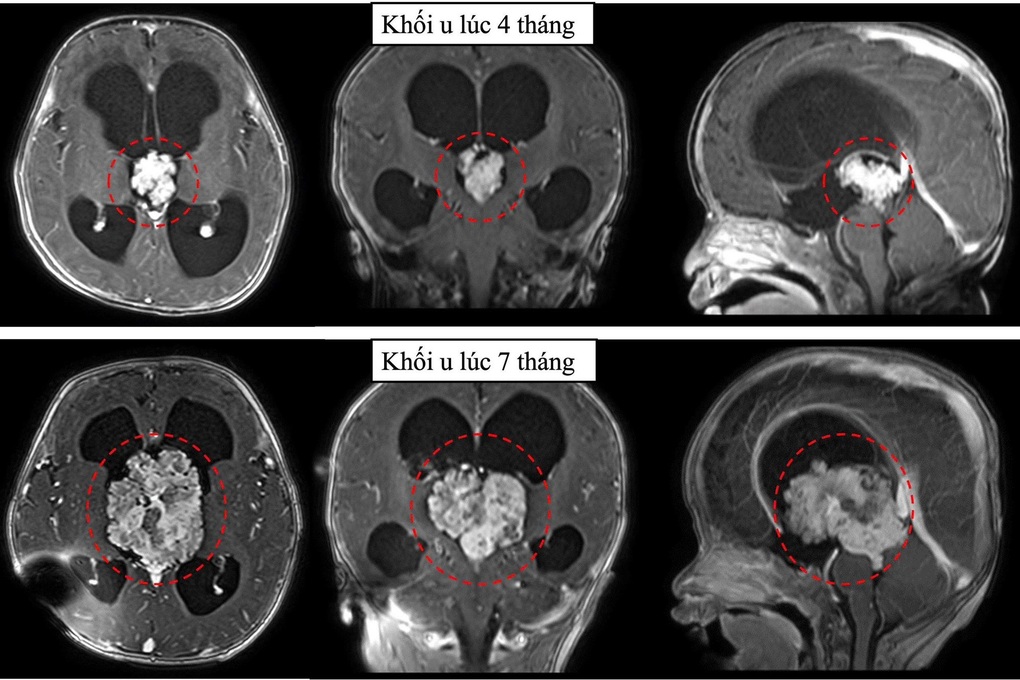

Nhưng 3 tháng sau, khi chụp phim cộng hưởng từ sọ não, bác sĩ phát hiện khối u tăng kích thước hơn gấp 3 lần. Không thể trì hoãn thêm, ê-kíp điều trị tư vấn gia đình việc phẫu thuật mổ lấy u để cấp cứu cháu bé.

Khối u tăng kích thước gấp 3 lần trong thời gian ngắn (Ảnh: BV).